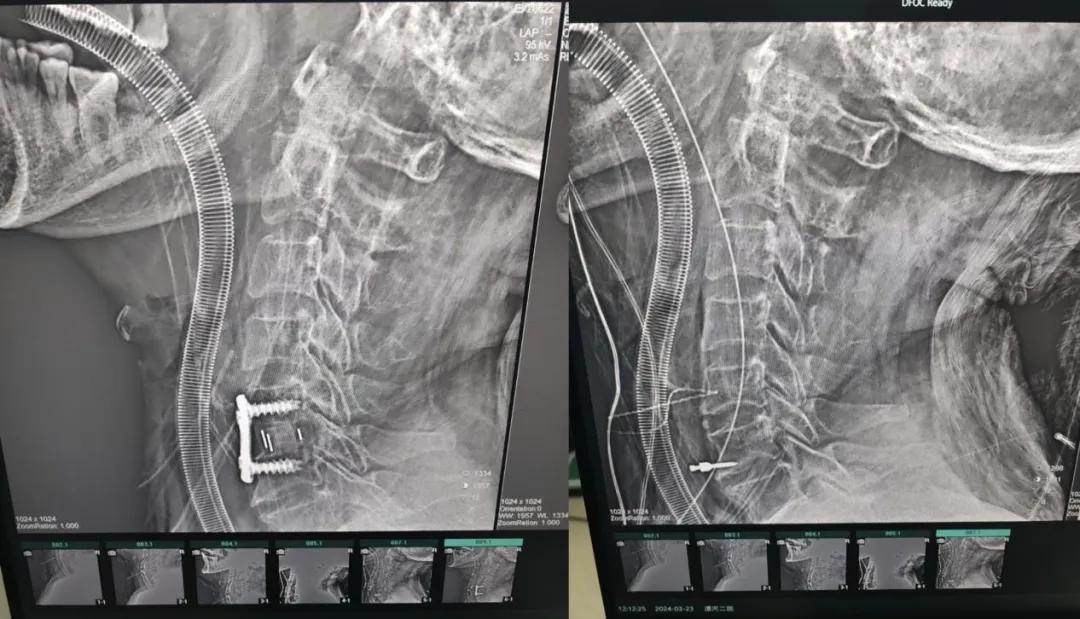

近日,70歲的馬阿姨,因摔傷后出現(xiàn)持續(xù)性頸部疼痛伴右側肢體無力、麻痛,影響日常生活。于是來到市二院神經(jīng)外科就診,經(jīng)檢查發(fā)現(xiàn):頸椎MR示:頸3/4、4/5、5/6、6/7椎間盤變性突出(中央型)并繼發(fā)性椎管變窄,頸椎退行性改變,頸5椎體水平頸髓水腫。神經(jīng)外科副主任劉沛濤根據(jù)患者癥狀、體征、影像學三者結合診斷為“脊髓型頸椎病”,考慮到患者癥狀逐漸加重、保守治療效果不佳等情況,建議盡快手術治療。

經(jīng)過縝密的術前準備和手術計劃,在鄭大一附院神經(jīng)外科張風江教授的指導下,神經(jīng)外科團隊順利為患者實施“顯微鏡下頸椎前路C5/C6椎間盤切除椎間融合+內(nèi)固定術”,手術時間不到1小時。術后患者恢復情況良好。